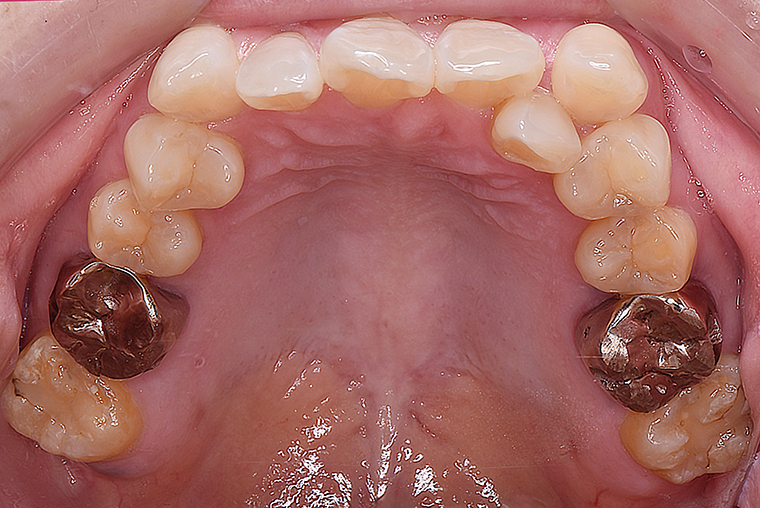

Case Study53歳女性ガタガタな歯のマウスピース矯正-矯正期間1年4ヶ月

BEFORE